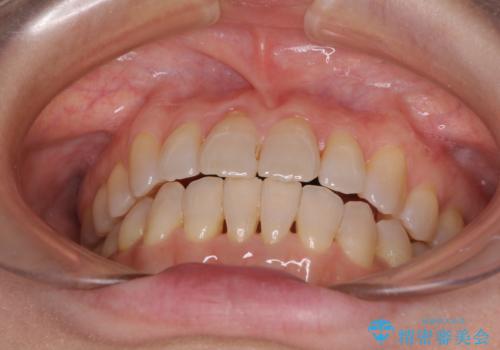

前歯の叢生と切端咬合 インビザラインによる矯正治療

- 前歯のデコボコを気にして来院された患者様です。

上下前歯の先端同士が接触する切端咬合であったため、上顎は歯列を拡大し、下顎はIPR(歯と歯の間を削る)により叢生を解消しながら歯列を小さくすることとしました。

切端咬合はスムーズに解消され、前歯の負担を軽減させることができました。